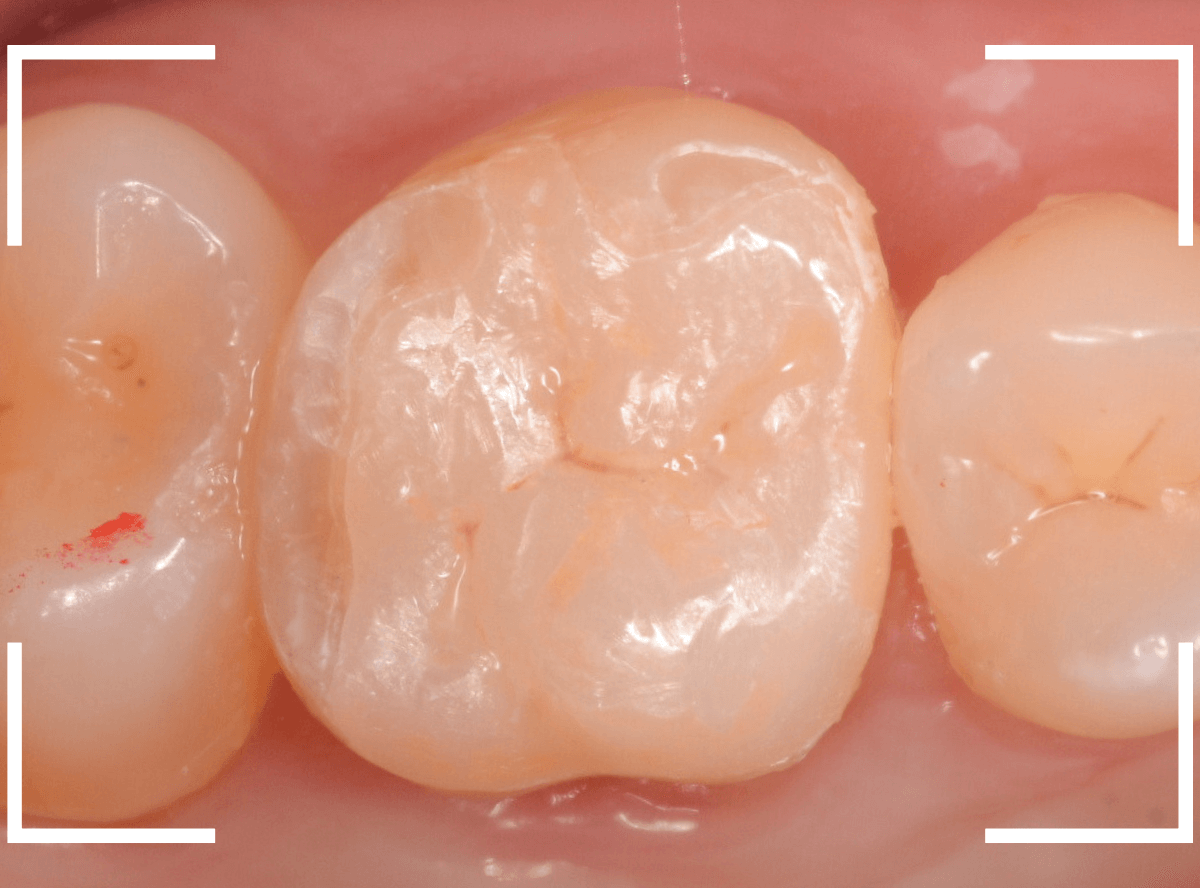

治療後の状態です。

ジルコニア・インレーはE-MAX・インレーより審美性に劣るのですが、患者さんにもご満足いただける仕上がりになり、ホッとしました。